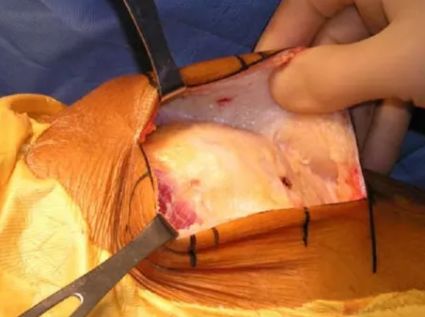

Gerdy结节截骨入路

入路同胫骨平台骨折的Gerdy结节截骨入路(如下示意图) 。平行于胫骨纵轴截取Gerdy结节骨块(大约1cm宽*2cm长*1cm厚)。然后将骨块连同其上附着的髂胫束向上翻转后能完全显露整个股骨外髁。

适用于Letenneur I、II、III型外髁Hoffa骨折,特别适合II型及外髁后部粉碎者。

该入路对外髁后部的显露较充分,可直视下由后向前打螺钉或完成支持钢板的固定。外髁Hoffa骨折固定完成后,再以带垫片的螺钉通过预先钻孔将Gerdy结节原位钉回(截骨前预钻孔!)。